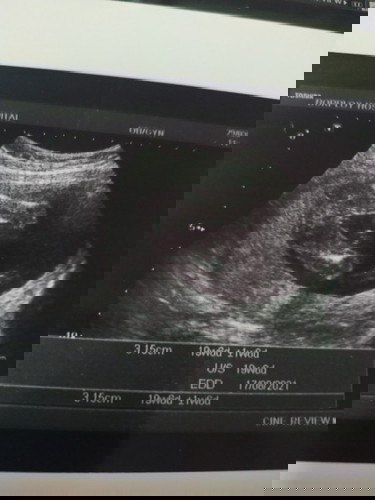

ผู้หญิงหรือผู้ชาย

ช่วยดูหน่อยค่ะ ว่าผู้หญิงหรือผู้ชาย 🥰